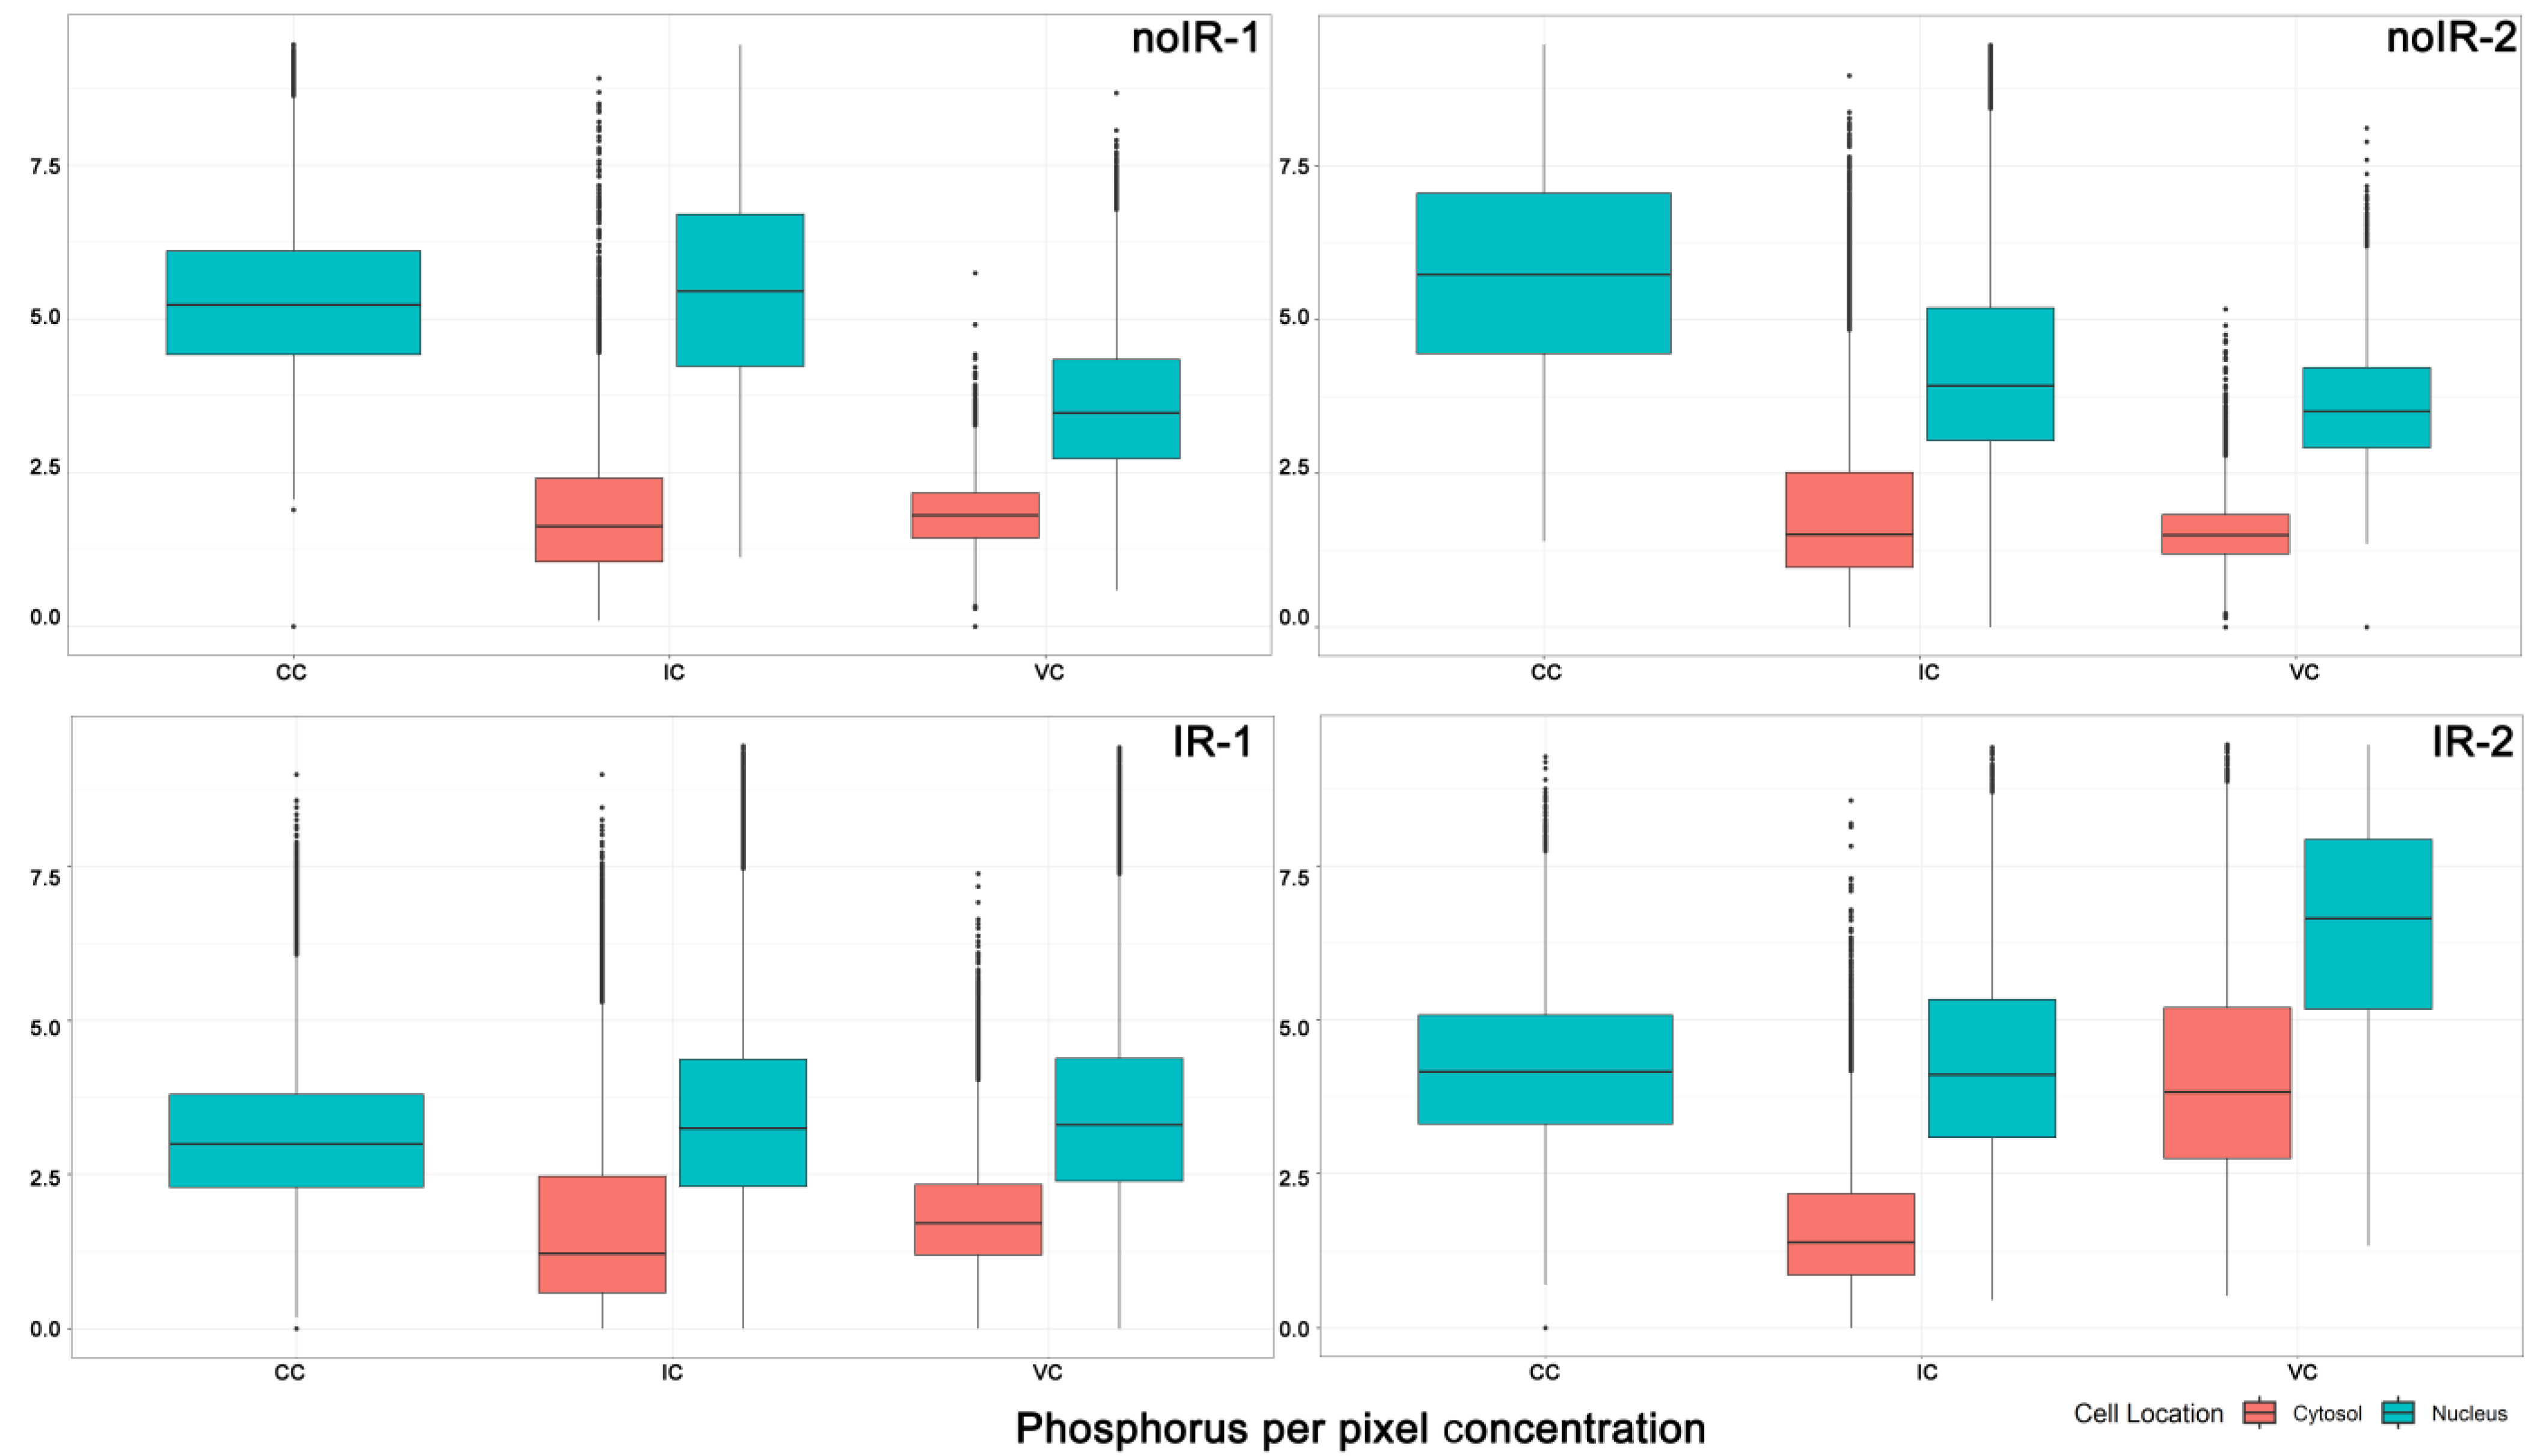

2.2. Statistical Analyses of ROI Data Extracted from XFM Images

2.2.1. Mean Pixel Concentration Analysis—Cell Type Analyses

2.2.2. Mean Pixel Concentration Analysis—Individual Cell Analyses

2.2.3. ANOVA Evaluation of Cell-to-Cell Elemental Differences

2.2.4. T-Test Evaluation of Differences between Different Scans of the Same Cells

2.2.5. Tissue Region Analyses